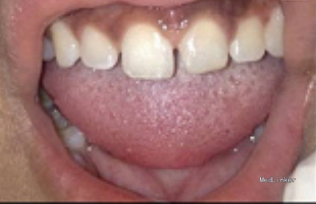

患者13岁,2月前出现上前牙的尖锐疼痛。十天前于当地医院进行21牙根管治疗,治疗过程中疼痛加重。

检查见21牙周围牙龈正常,无瘘道,叩(+)。 X线片发现21牙根中部有一髓石,牙冠颈部也有一髓石。